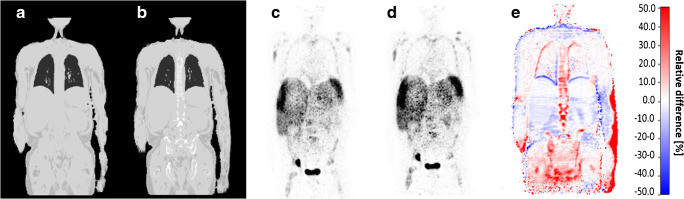

Figures 3, 4, and 5 show the 4-compartment μ-map and the 6-compartment μ-map with corresponding corrected PET data and calculated relative PET difference images. In all patient examples, the improved μ-map works robust, independent of the choice of radiotracer (Figs. 3 and 4). HUGE truncation correction results in a realistic body contouring adding tissue volumes along the arm regions and major bones to the standard Dixon-VIBE AC map. The color bar of the difference maps (Figs. 3, 4, and 5) provides the quantitative bias in percentage of relative undercorrection (red) or overcorrection (blue) when compared to the reference 4-compartment μ-map. As to be expected, the largest differences (relative undercorrection by the 4-compartment μ-map, red) are located in regions that profit from the addition of the bone model and the addition of previously truncated areas along the patient’s arms. Blue color indicates relative overcorrection by the 4-compartment μ-map (blue) in regions that profit from improved scatter correction due to introduction of the 6-compartments. Namely, the thoracic and pelvic body regions show light blue areas indicating the effects of improved scatter correction.

Fig. 3.

Patient example with injected 18F-FDG: standard 4-compartment μ-map serving as reference (a) and improved 6-compartment μ-map (b). c and d show corresponding attenuation-corrected PET data ((c) 4 compartments, (d) 6 compartments). c and d show no visible difference. e shows a calculated relative PET difference map, highlighting differences with color. The colored bar in (e) provides the quantitative bias of relative undercorrection (red) or overcorrection (blue) when comparing PET data corrected with 6-compartment μ-map to PET data corrected with a 4-compartment μ-map (reference). Maximal relative differences are observable in the previously truncated areas along the arms and in areas where bone was added to the μ-map

Fig. 4.

Patient example with injected 68Ga-DOTATOC: standard 4-compartment μ-map serving as reference (a) and improved 6-compartment μ-map (b) with corresponding attenuation corrected PET data (4-compartment (c), 6-compartment (d)). e A calculated relative PET difference map. Maximal relative differences between the 4- and 6-compartment AC PET data are observable in the truncated and bony areas also for this non-FDG tracer example

Likewise, the addition of truncation correction to the 4-compartment standard μ-maps had measureable quantitative impact on the increase of SUVmax of selected lesions in this study. This has also been demonstrated in previous studies by Blumhagen et al. [10], by Lindemann et al. [11], and by Oehmigen et al. [12]. In the present study, the highest impact of HUGE truncation correction on PET was quantified in lesions close to the arms. However, in the remainder of the body (e.g., thorax, shoulders, and hips), also bias in PET activity quantification was measurable. Accordingly, the relative difference images (Figs. 3 and 4) show that the relative impact of improved AC is mostly increased in the thoracic and pelvic region. Adding volumes of soft tissue in patients’ upper arms relative to the less attenuating large volume of lung tissue results in substantial relative gains of total tissue attenuation in the thoracic region. Also the pelvic region benefits from extended MR FOV due to HUGE because of the patients’ arm posture in PET/MR. Here, HUGE adds tissue volume along the patients arms to the μ-map in previously truncated regions. In addition, the 5-compartment μ-map adds the pelvic bones and the femurs in the pelvis, as well as the spine in the thorax to the μ-map. Thus, major bones with relatively high attenuation values are added to these regions. Consequently, the six lesions that showed highest relative difference of SUVmax due to the impact of adding bone tissue and truncation correction to the MR-based μ-maps were located in both of these body regions: the thorax and the pelvis (Table 2).

Calculated difference maps between 4 compartment and 6 compartment on Figs. 3, 4, 5, and 6 exhibit a relative undercorrection of PET signal in the 4-compartment μ-maps due to missing bone information and truncated arms (red color). The blue areas in the difference maps (e.g., in the thorax and pelvis) are the results of improved scatter correction when applying the 6-compartment AC as also reported in the studies by Lindemann et al. [11] and by Oehmigen [12]. Scatter correction in PET/MR is also based on the AC maps. Thus, the incorporation of the bone model and information from extended MR FOV in the 6-compartment AC map also affects scatter correction from these two additional compartments. Therefore, this results in a more realistic scatter estimation when applying the improved 6-compartment μ-maps (blue color).